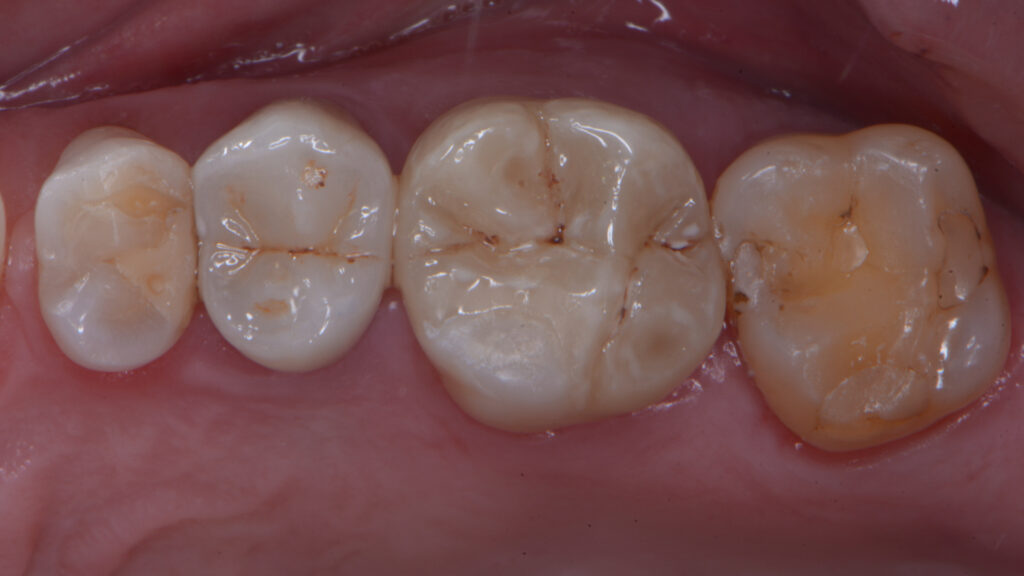

Paziente di 55 anni, presenta il 1° quadrante con gravi problematiche restaurative/endodontiche in particolare processi cariosi multipli ai danni degli elementi 1.4 - 1.5 - 1.6 - 1.7.